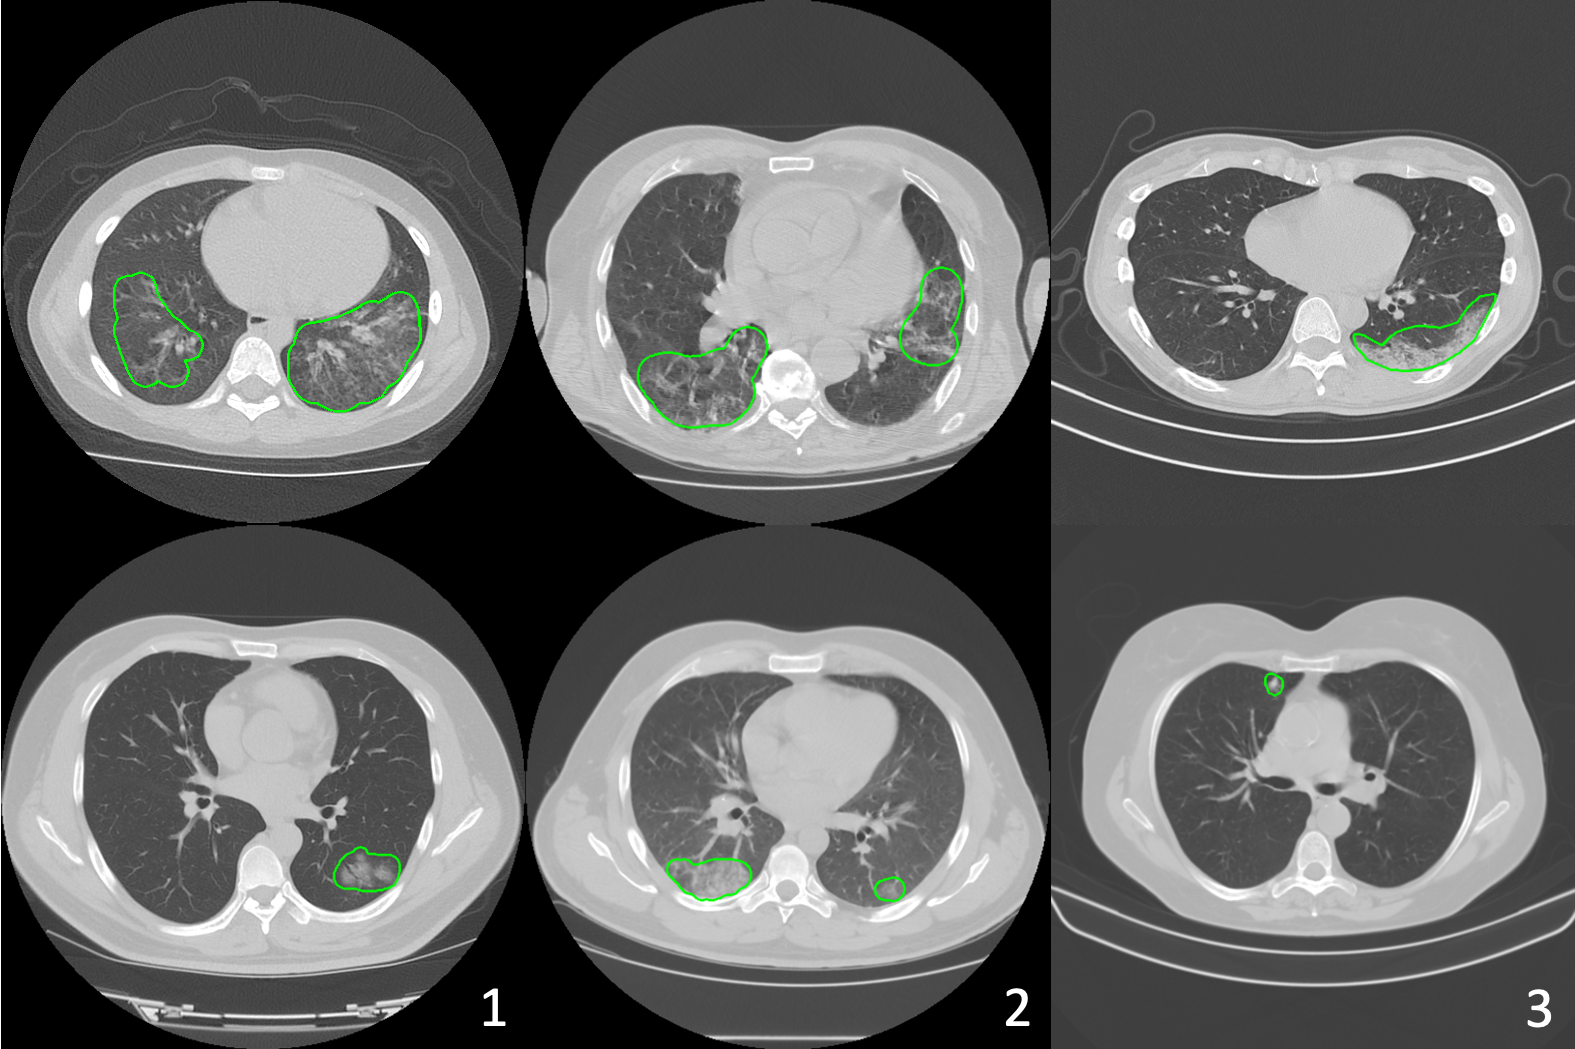

Refer to caption

Figure 5: Visualizations of federated semi-supervised segmentation of COVID regions in 3D CT (from the testing set of unsupervised client Image_2). “Non-FL” indicates results from the model trained with Image_1 along, and “FL” denotes results from the model trained with federated semi-supervised learning on Image_1 and Image_2. The segmentation results using the proposed framework captures the ground truth shapes better and has less false positives.

Federated semi-supervised learning has approximately 1%percent11\% Dice’s score drop compared to supervised FL. However, the model performs better than the model trained on Image_1, Image_2, or Image_3 independently in general (see the testing results on Image_2 and Image_3). It demonstrates that the unlabeled data from different clients are valuable to train a generalizable model. The visual results are shown in Fig. 5, and our model predicts segmentation masks with better shape and less false positives.